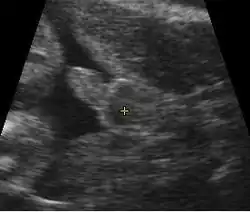

Première échographie

L'échographie au premier trimestre de la grossesse permet :

- de s'assurer de la vitalité de la grossesse par la présence d'un embryon présentant une activité cardiaque ;

- d'affirmer le caractère unique de l'embryon ou multiple. S'il existe deux embryons, il s'agit d'une grossesse gémellaire. En cas de grossesse gémellaire il est important pour le suivi correct des grossesses de savoir s'il existe un placenta ou deux placentas qui alimentent l'embryon. On parle dans ce cas de grossesse monochoriale s'il existe un placenta (absence de signe du lambda) et de grossesse bichoriale s'il existe deux placentas (signe du lambda présent) ;

- de dater le début de grossesse en mesurant la longueur de l'embryon (longueur craniocaudale), avec une précision de l'ordre de 7 jours[27] ;

- d'évaluer le risque que l'embryon soit porteur d'anomalie chromosomique comme la trisomie 21 par mesure de la clarté nucale ;

- de voir certaines malformations ou pathologies à expression échographique précoce.

Deuxième échographie

Troisième échographie

Beaucoup de pays ne font pas systématiquement de troisième échographie. En France, une troisième échographie est faite idéalement entre 7 mois et 7,5 mois soit 32 à 34 semaines. Elle permet :

- de vérifier la croissance (Dépistage des retards de croissance d'apparition tardifs ou des macrosomes) ;

- de s'assurer du bien être fœtal ;

- de dépister un placenta inséré bas ;

- de s'assurer de l'absence de certaines malformations à traduction échographique tardive ;

- de s'assurer de la culbute physiologique du fœtus c’est-à-dire de la position tête en bas. En cas d'absence de culbute physiologique, la culbute sera vérifiée deux semaines plus tard. Si la version spontanée ne s'est pas fait on proposera à la patiente une version par manœuvre externe.